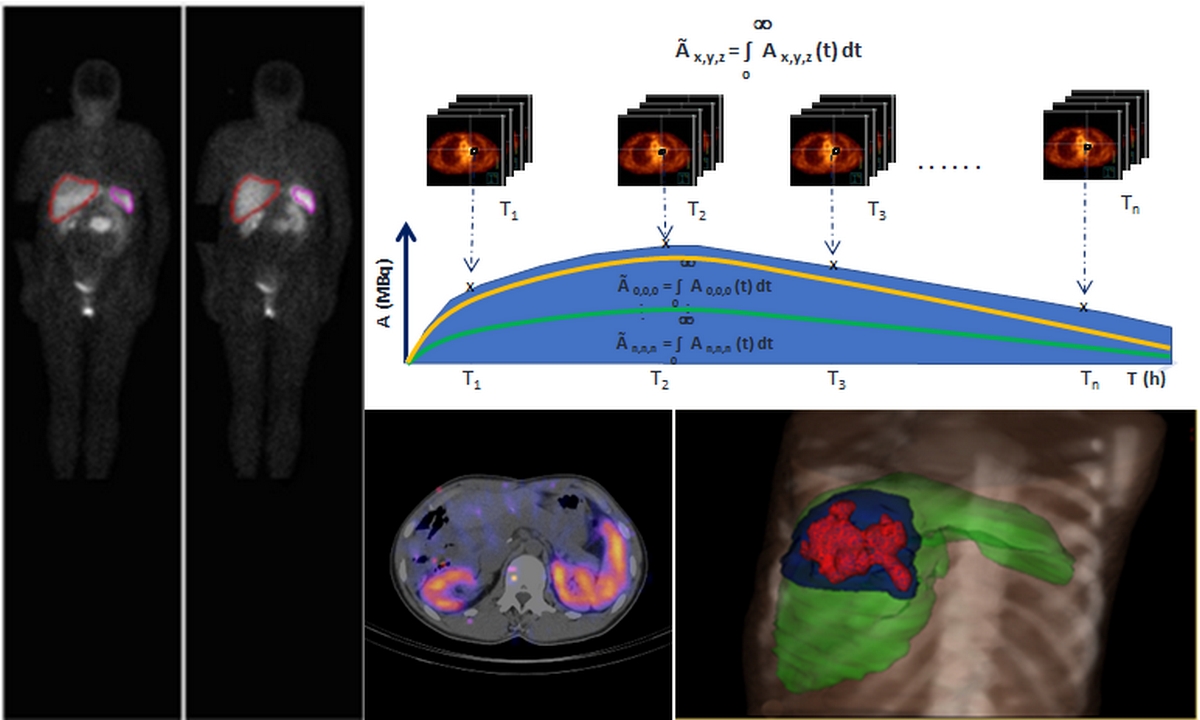

Radiopharmaceutical therapy (RPT) has demonstrated unique therapeutic advantages in the treatment of an increasing number of cancers. As with other treatment modalities, there is related toxicity to a number of organs at risk. The clinical benefit of performing dosimetry has now been demonstrated for a number of nuclear medicine therapies. However, propagation of dosimetric methods into nuclear medicine practice remains slow and considerable uncertainties in absorbed dose calculations still exist. Harmonized dosimetric protocols and methodologies should guide a personalized patient treatment with the aim of improving efficacy and reduce toxicity. The International Atomic Energy Agency (IAEA) is about to initiate a CRP on Dosimetry in RPT to support the standardization and dissemination of dosimetric methods in nuclear medicine therapy. The CRP will assist Member States in testing and adopting harmonized dosimetric protocols and to assess the typical accuracy with which dosimetry can be reached in nuclear medicine practice. State of the art research in the field will be implemented, with a direct impact to both the clinical services and the research potential of the Member States.

Radiopharmaceutical therapy (RPT) has demonstrated unique therapeutic advantages in the treatment of an increasing number of cancers. The overall objective of this project is to enhance the capabilities of Member States to incorporate dosimetry in RPT practice. The ultimate benefit will be to patients receiving individualized RPT so as to make this treatment modality safer and more effective.

The overall objective of this project is to enhance the capabilities of Member States to incorporate dosimetry in RPT practice. The ultimate benefit will be to patients receiving individualized RPT so as to make this treatment modality safer and more effective.

1. Establish an understanding of tools and methods available for dosimetry of RPT 2. Assess and investigate ways to improve the achievable accuracy of tumour and normal tissues absorbed doses 3. Create scientific networks with expertise in dosimetry for RPT that will remain active after the completion of the CRP 4. Support participating institutes to become reference centres on RPT for their Member States 5. Identify the advantages of implementing dosimetry in terms of reducing toxicity and improving tumour response